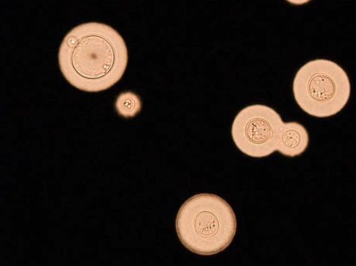

Cryptococcus has several virulence factors that enable evasion of host defenses:

- Polysaccharide capsule: Antiphagocytic; immunomodulatory

- Melanin production: Antioxidant protection

- Ability to survive within macrophages: Trojan horse mechanism for CNS penetration

- Titan cells: Large cells resistant to phagocytosis

| India ink | Positive in ~75–85% of cases |

| CSF India ink | 75-85% | >95% | Visualizes capsule; less sensitive |